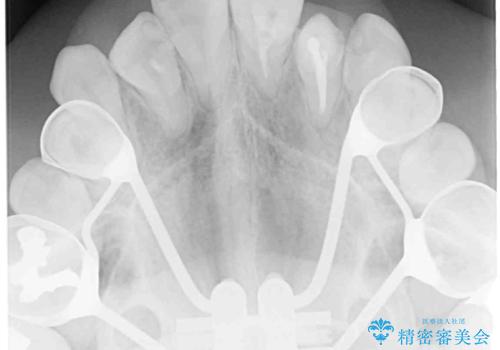

狭い上顎骨を拡大 インビザラインによる非抜歯矯正

上顎骨の幅が下顎骨よりも小さいので、拡大装置により骨幅を広げて上下関係を改善し、その後インビザラインにて歯並びを整えることとしました。